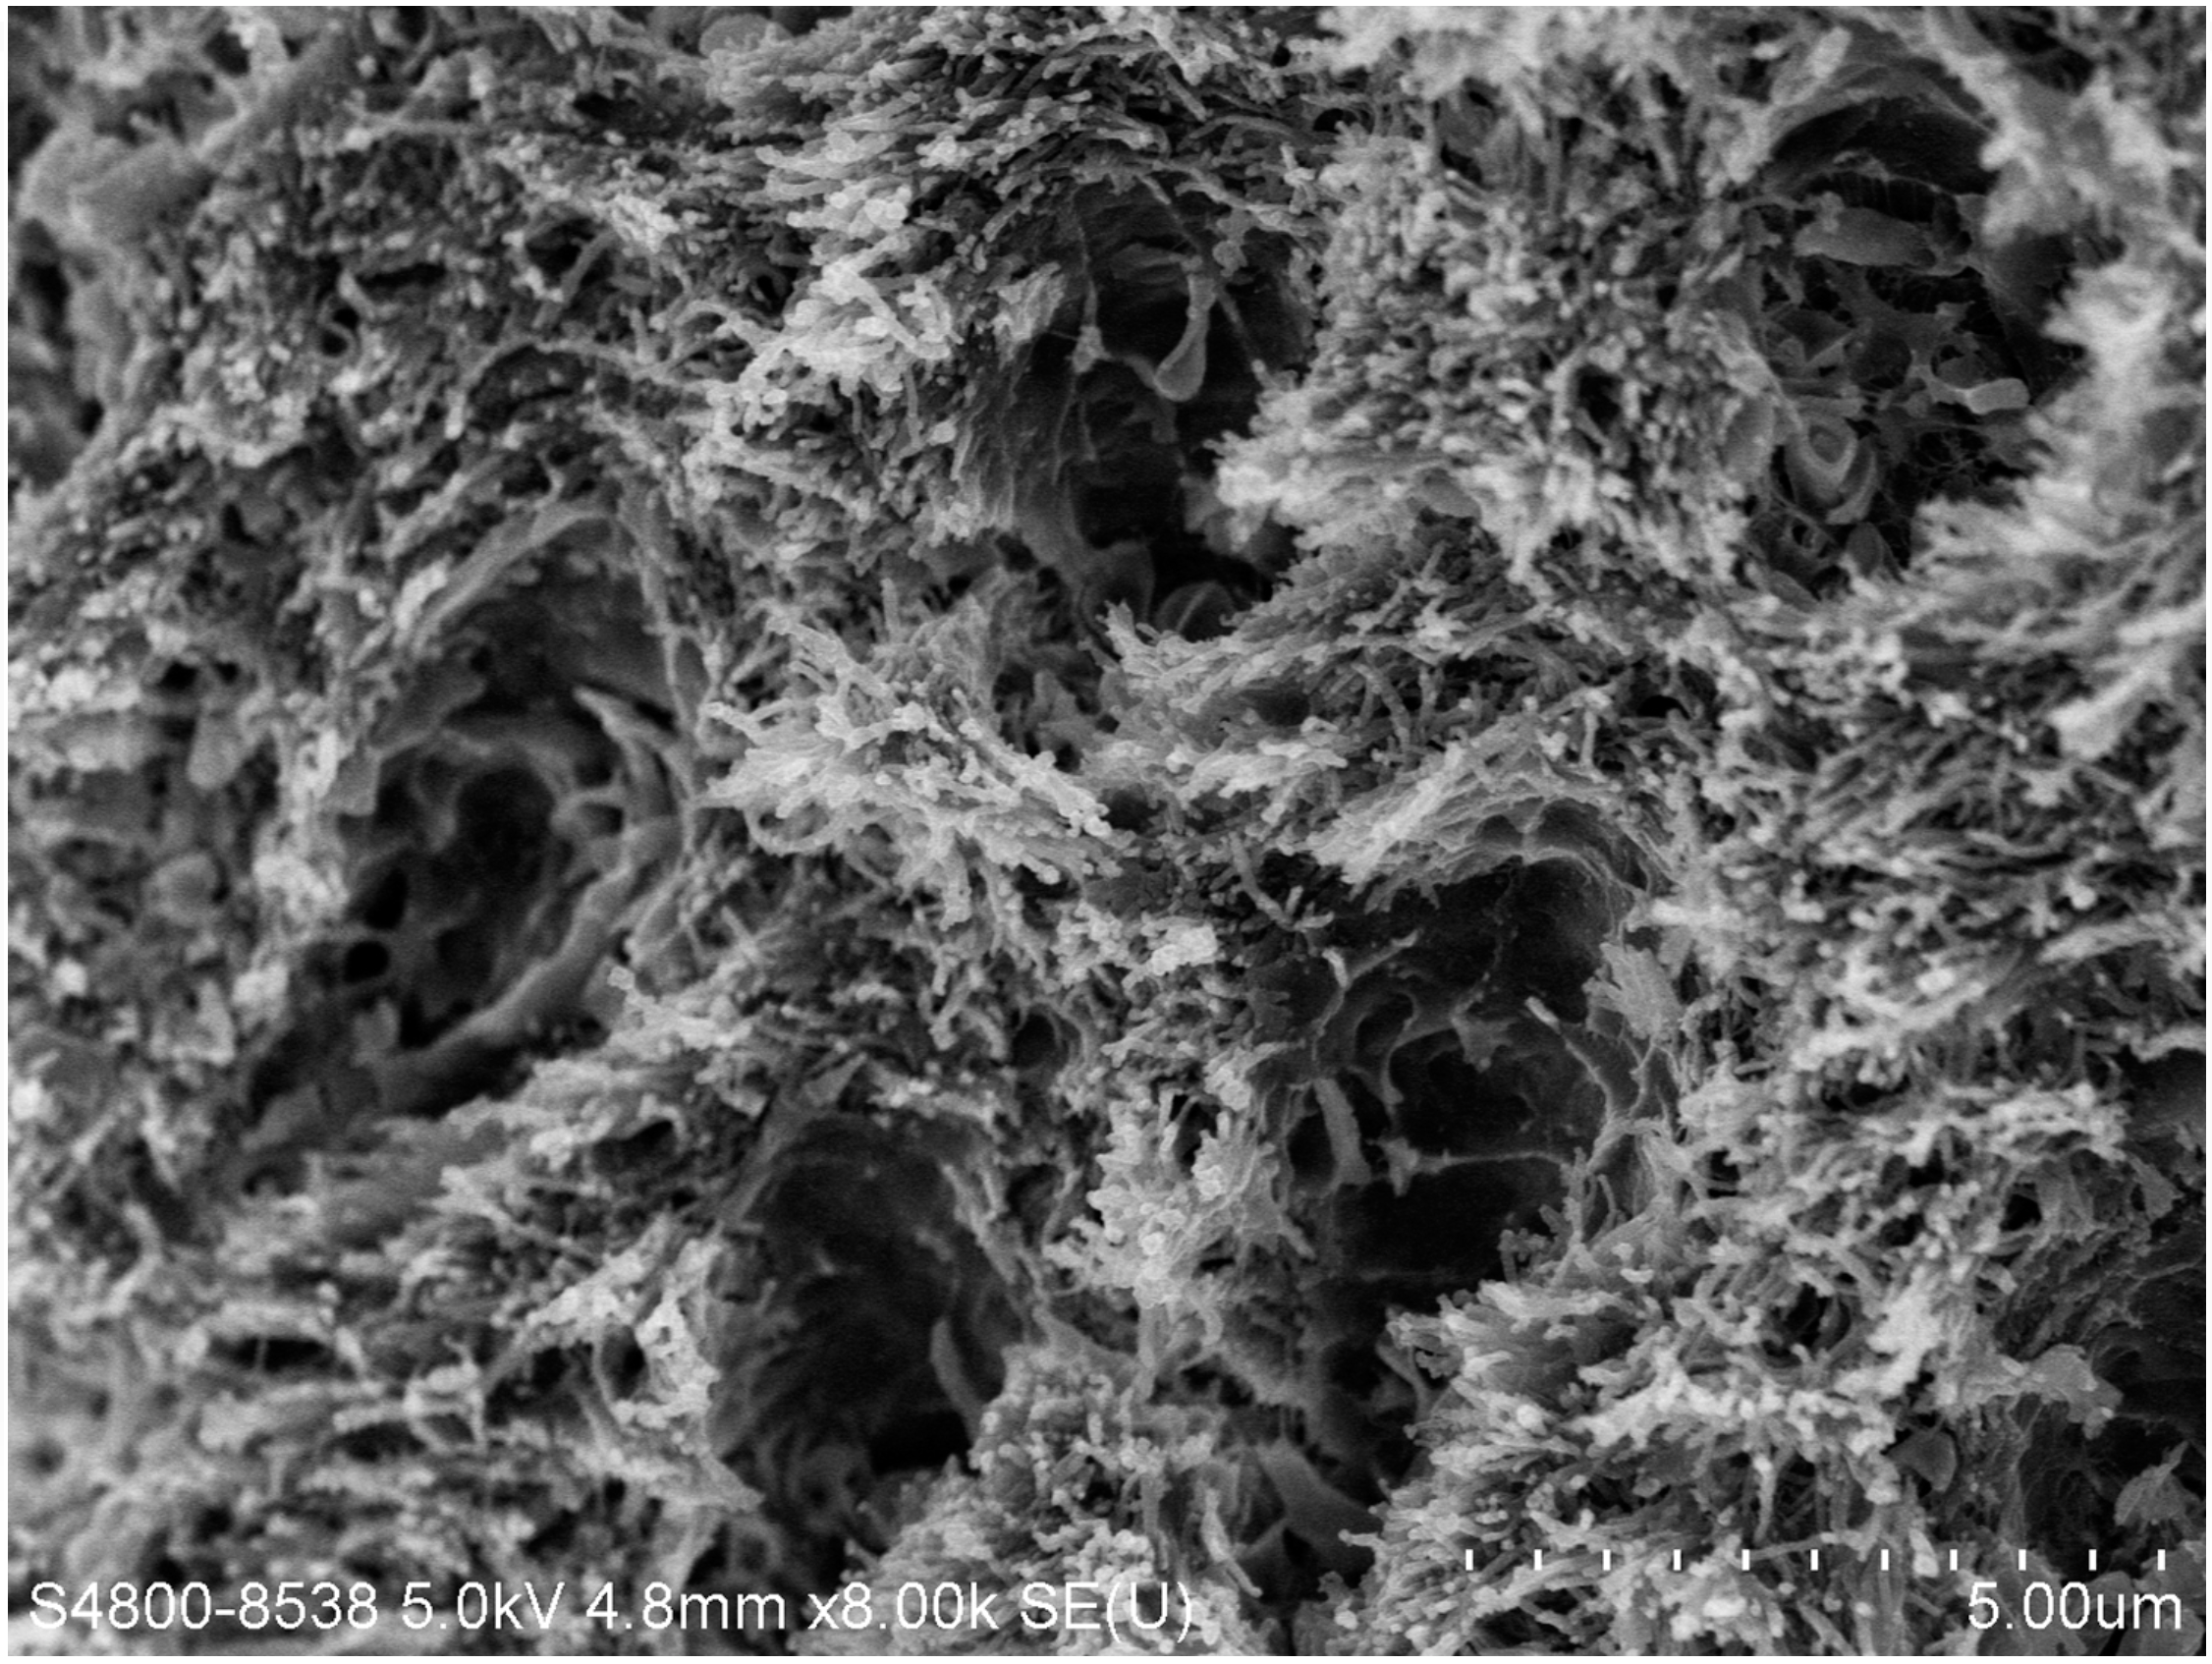

There are several advantages of using SDF in dental treatment. First, it showed an antimicrobial activity against mono-species, dual-species, and multi-species cariogenic biofilm.14-16 Silver ions are bactericidal metal cations that inhibit biofilm formation.17 Studies have indicated that silver interacts with sulfhydryl groups of proteins and DNA, thus altering hydrogen bonding and inhibiting respiratory processes, DNA unwinding, cell-wall synthesis, and cell division.18 At the macro level, these interactions affect bacterial killing and inhibit biofilm formation.17 Second, fluoride promotes caries lesion remineralization. Fluoride has been indicated to react with hydroxyapatite and generate calcium fluoride, which is a reservoir of fluoride, and facilitate further remineralization.19 An ex vivo study reported surface microhardness of the surface layer of the arrested caries after SDF applications was comparable with the unaffected sound dentin20 (Figure 1 and Figure 2). This is consistent with another study, in which a high remineralized zone was observed on the surface of arrested caries from exfoliated teeth with SDF treatment21 (Figure 3 and Figure 4). Third, its application procedures are simple and do not require injection or drilling, and the treatment does not involve expensive support infrastructure equipment such as piped water and electricity. The simplicity of the treatment is conducive to treating caries in apprehensive young children who may have intense dental fear, uncooperative patients with special needs, or elderly patients who have difficulty adapting to traditional dental care. It also allows trained workers to deliver the treatment to people who live in the area but who may not be able to easily access dental service.22 Patient compliance and satisfaction is often good when the patient is provided a clear explanation of the treatment outcome.23,24 Finally, the cost of SDF treatment is low and should be affordable in most communities.

Fig 3. Scanning electron microscope (SEM) images of the dentin carious lesions: surface morphology of arrested carious lesion. (image

from Mei, et al, 2014, ref 21 [reprinted with approval])

Figure 3

Fig 4. Scanning electron microscope (SEM) images of the dentin carious lesions: surface morphology of active carious lesion. (image

Figure 4